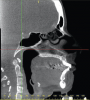

Figure 9A  An example of orthodontic and orthognathic surgery being performed without adequate goals. A) The maxillary central incisors were positioned with severe protrusion. The tooth has been moved through the cortical bone, has forces directed nearly perpendicular to the long axis, and shows evidence of root resorption.

Figure 9A

Figure 9B An example of orthodontic and orthognathic surgery being performed without adequate goals. B) Tomographic evidence of degenerative joint disease and condyles positioned distal to the center of the fossa.

Figure 9B